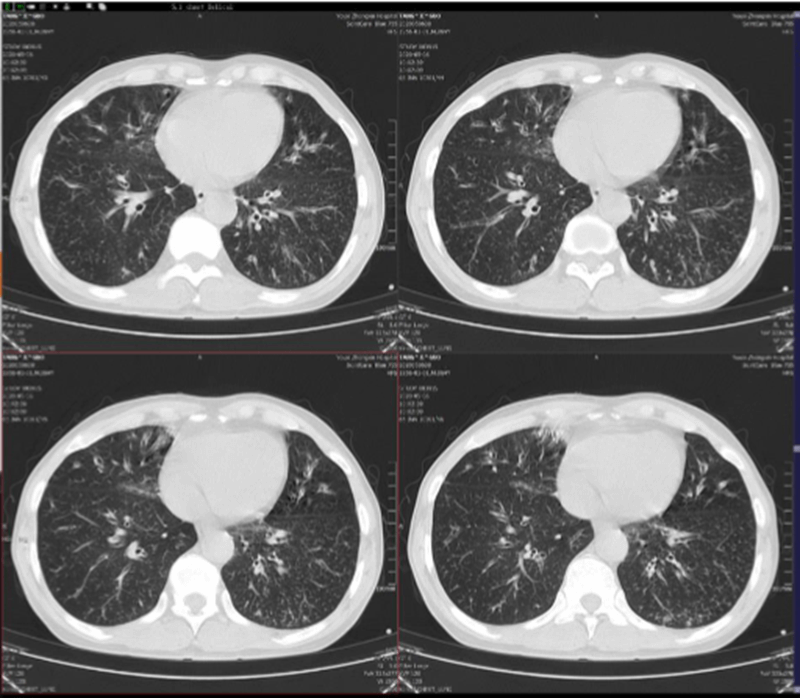

Scanner thoracique: modifications interstitielles, bronchectasie